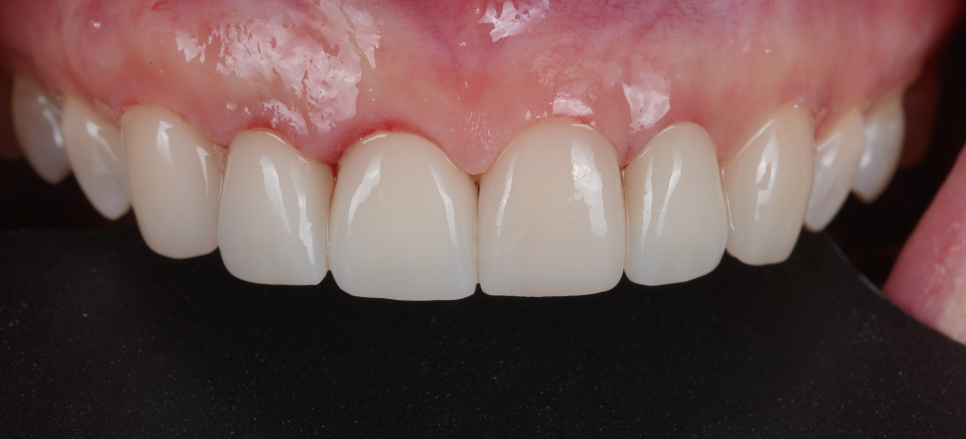

최종 보철을 완성한 뒤, 환자분께서 요청하신 잇몸 라인과 균일한 치아 색상, 자연스러운 치아 형태가 잘 구현되었는지 확인했습니다.

또, 혀에 걸리는 느낌이나 불편한 부위는 없는지, 전체적인 교합 상태까지 면밀히 점검하며 세밀한 조정을 거쳐 치료를 마무리했습니다.

보철을 모두 세팅하고 거울을 보시던 순간 한참 말이 없으시더니 “수원에서 왔다 갔다 하는 게 사실 좀 힘들었는데 그동안의 고생이 싹 잊히네요~"라고 하시더라고요ㅎㅎ

251224

이 치료의 목표는 무조건 하얗게 만드는 것도, 화려하게 만드는 것도 아니었어요.

환자분의 콤플렉스를 해결해 주고 자연스러운 미소를 만들어 드리는 것 그게 전부였어요.

처음 오셨을 때와 달리 나가시는 발걸음에서부터 기분이 좋아 보이셨는데요. 앞으로 관리 열심히 하셔서 오래 사용하셨으면 좋겠습니다!

251105 - 251224